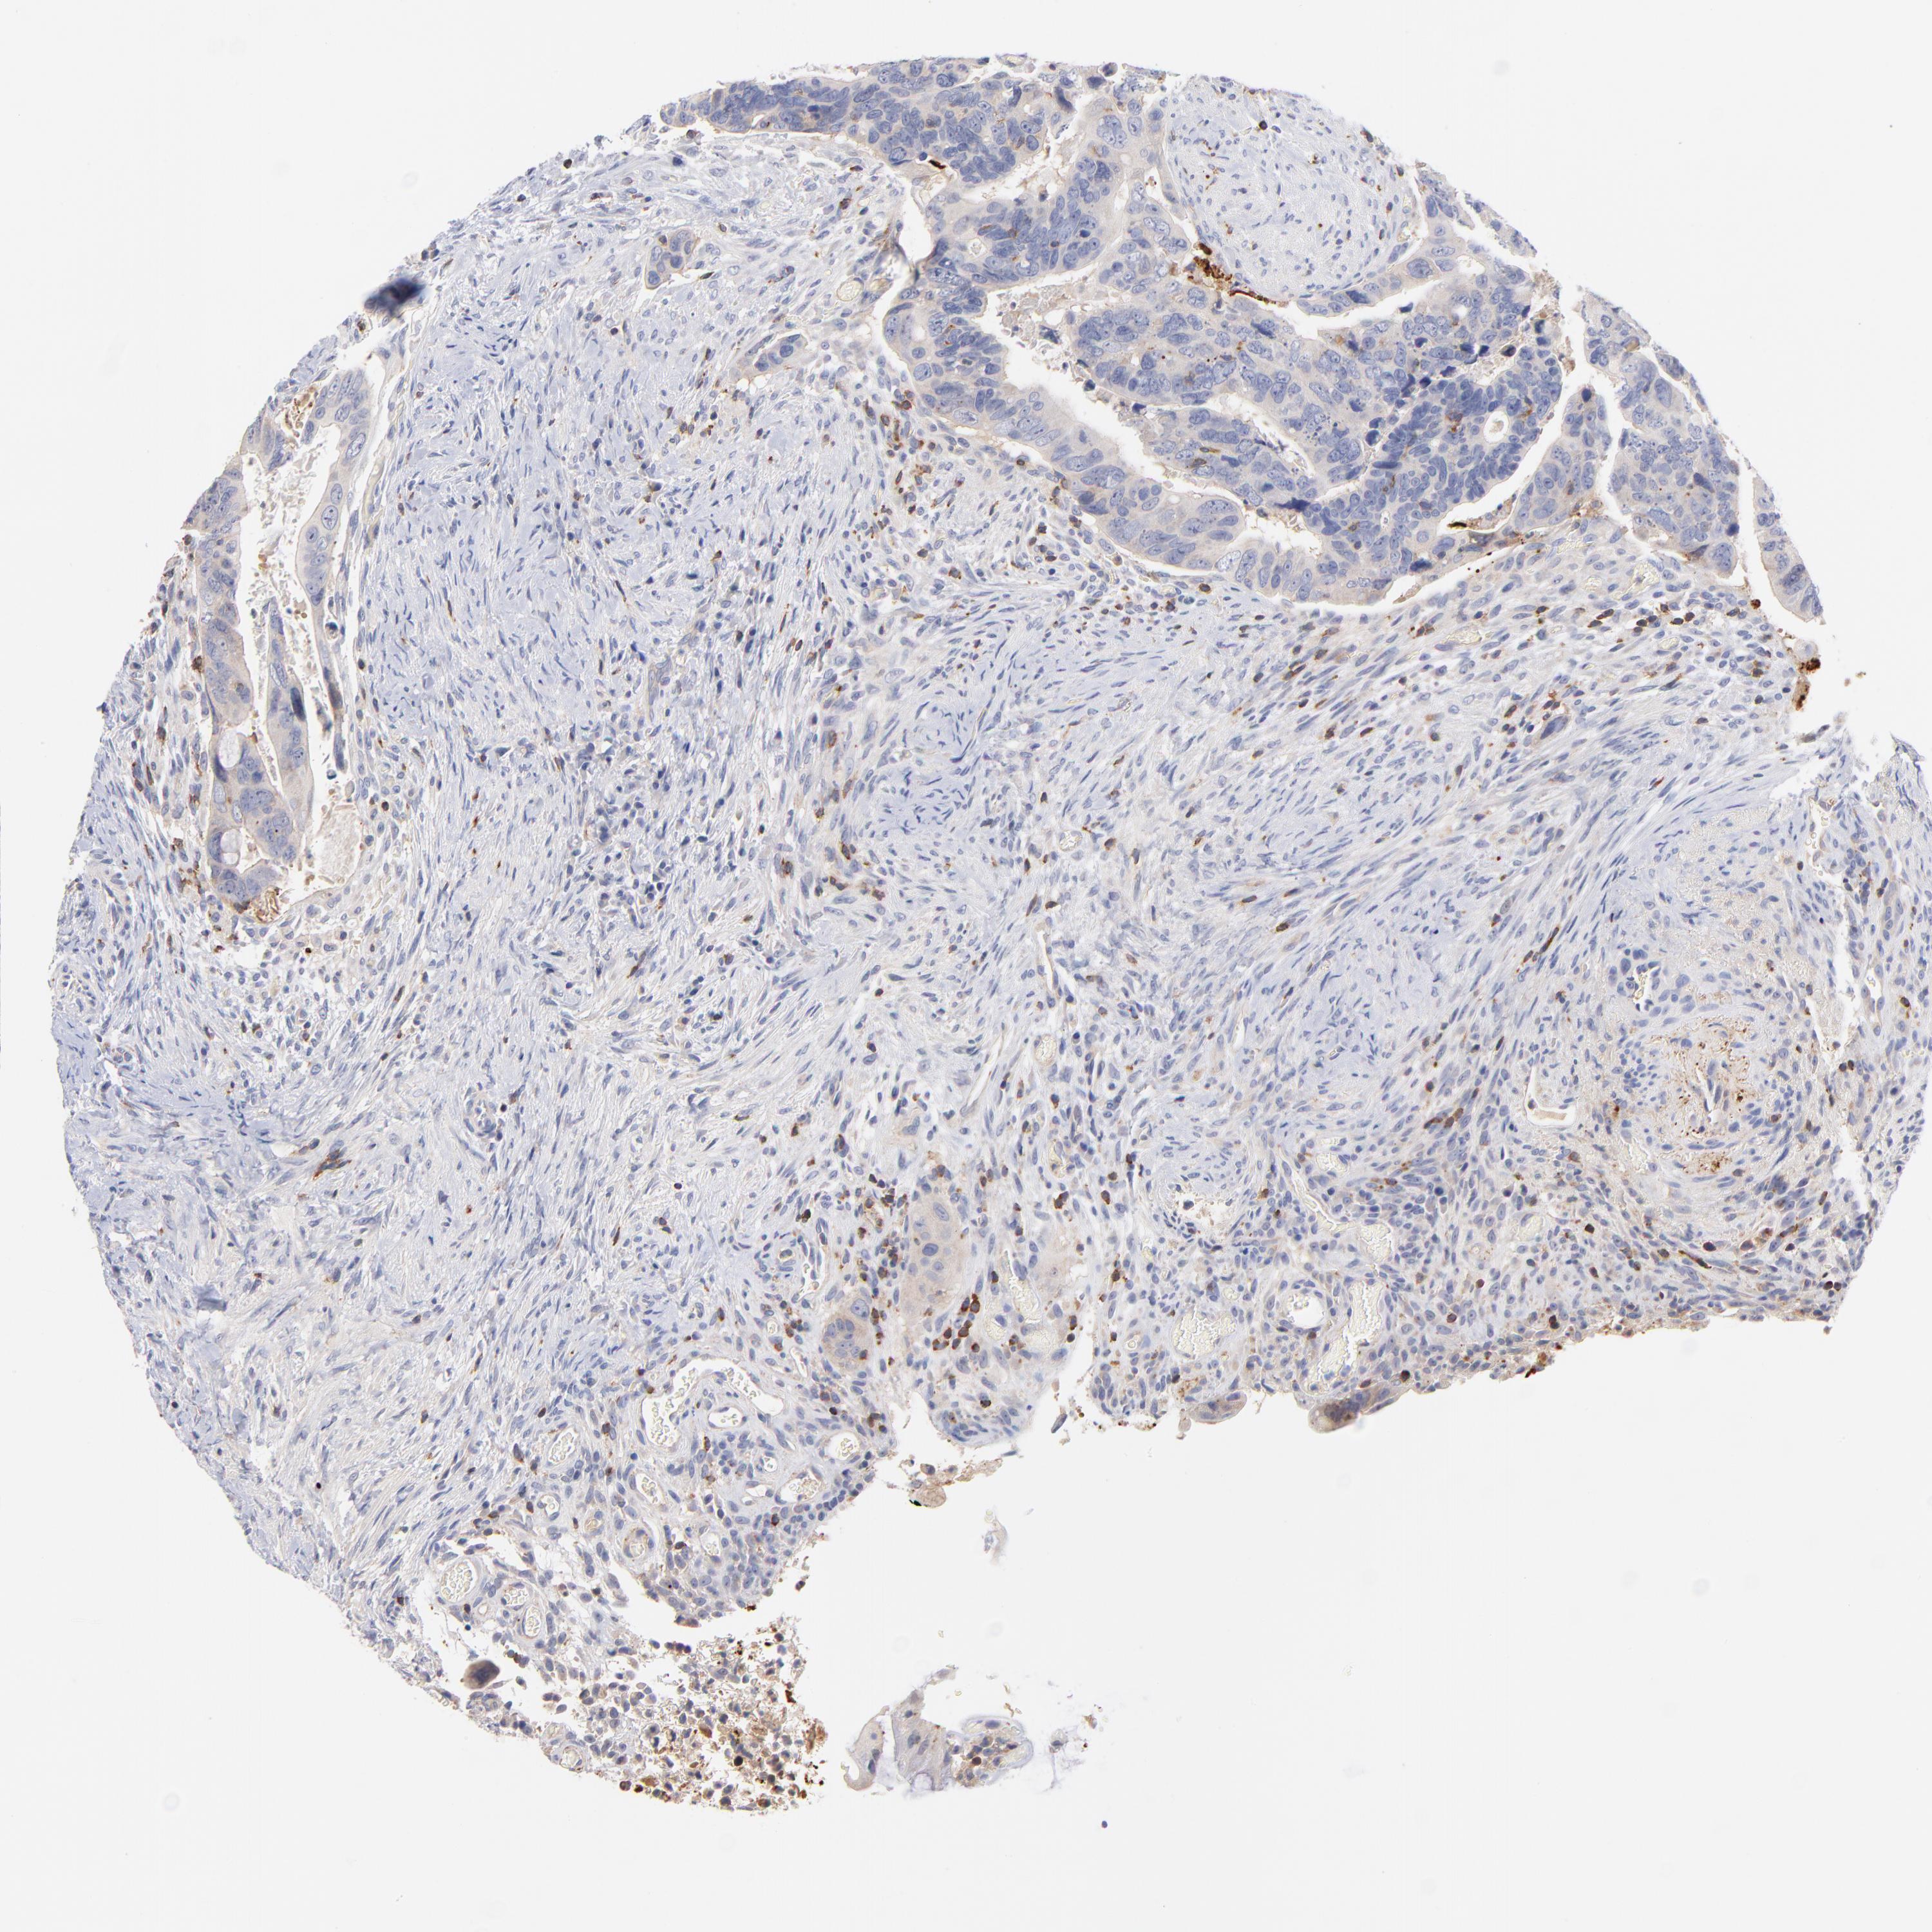

CANCER COLORECTAL CANCER Show tissue menu

Colorectal cancer

Colon adenocarcinoma

KREMEN2 is not prognostic in Colon Adenocarcinoma (validation)

KREMEN2 is not prognostic in Rectum Adenocarcinoma (TCGA)